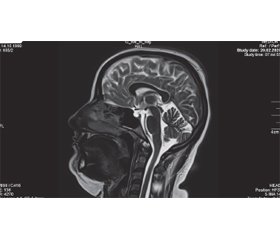

МРТ головного мозку: дані наведені на рис. 1–3.

Синдром церебральної псевдопухлини на МРТ головного мозку характеризується відсутністю мас-ефекту, незміненими розмірами шлуночків поряд із непрямими ознаками внутрішньочерепної гіпертензії: порожнім турецьким сідлом, опущенням мигдаликів мозочка у великий потиличний отвір, сплощенням заднього полюса склер, звивистістю зорових нервів, розширенням субарахноїдальних періоптичних просторів, інтраокулярною протрузією преламінарної частини зорового нерва [7].